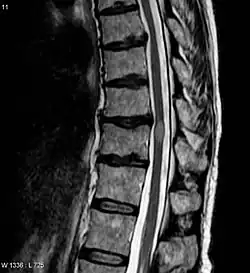

- МРТ всего позвоночника с контрастным усилением и без него (Данное исследование позволит оценить насколько большой очаг поражения, выявить признаки воспаления. А также исключить сдавление спинного мозга, при котором возможно оперативное лечение)

- МРТ головного мозга с контрастным усилением гадолинием и без него. (Для оценки наличия очагов демиелинизации в головном мозге, что может указывать на рассеянный склероз)

- Большие очаги или несколько очагов в спинном мозге на МРТ

- Поражения головного мозга на МРТ